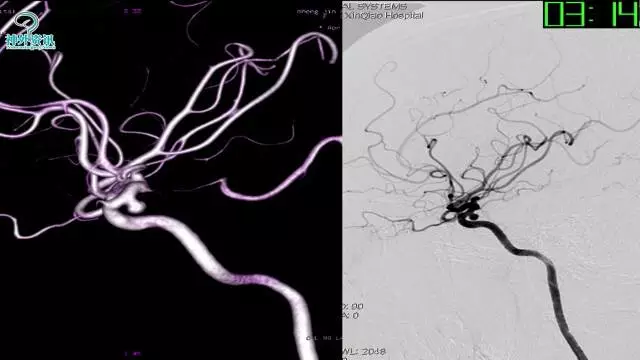

今天为大家分享的是“强生医疗CNV-神经介入专栏”第三十六期,由重庆第三军医大学附属新桥医院神经外科刘俊带来的“Galaxy弹簧圈在不规则动脉瘤中的临床应用”精彩讲课视频及PPT,欢迎观看。文章仅代表作者个人观点,如有不同见解,欢迎同道斧正!